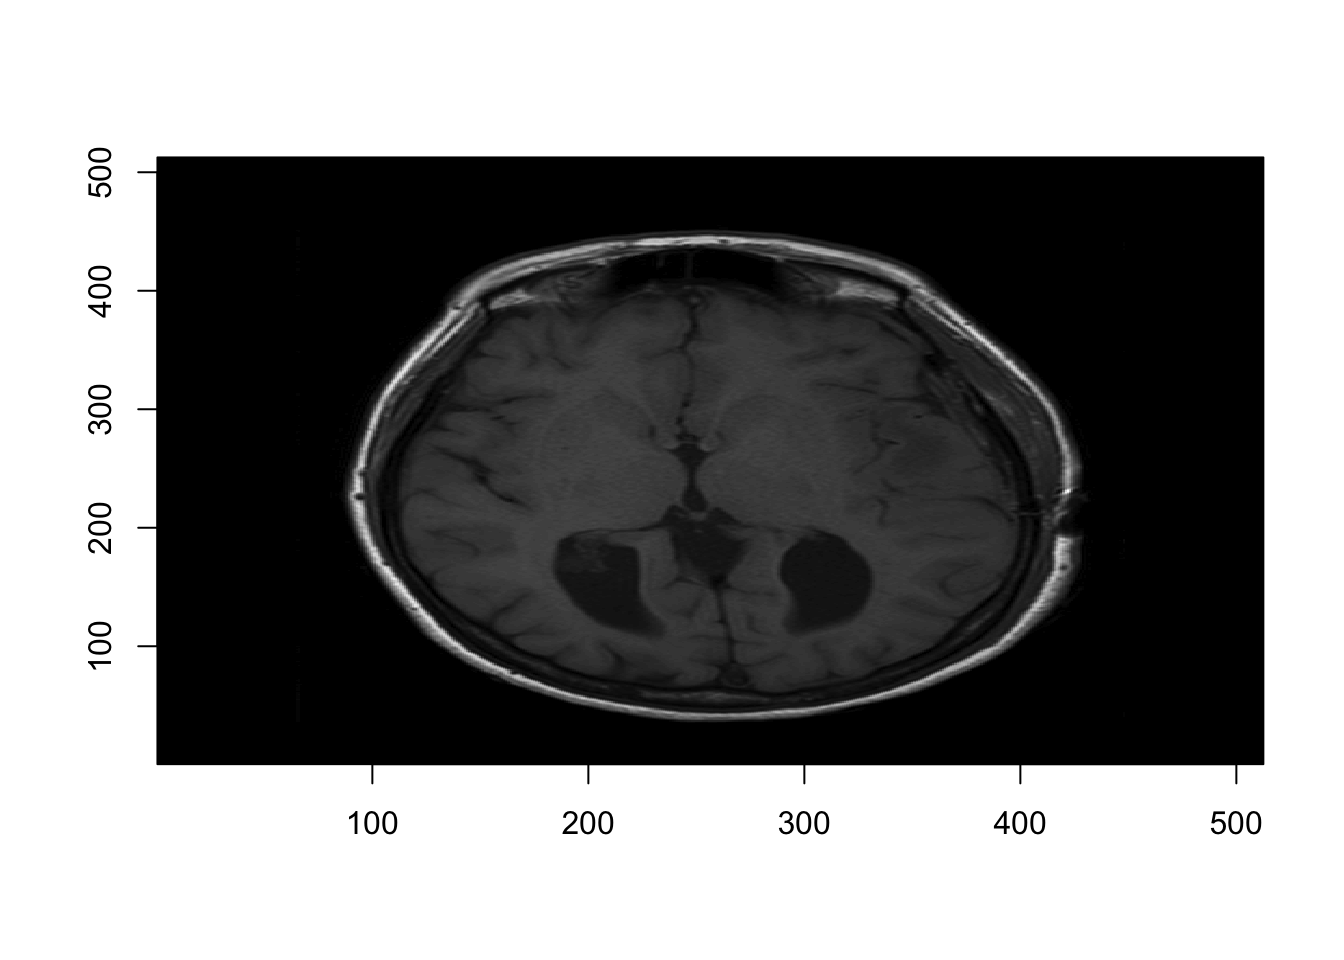

As a first pass, we could use the image function from the graphics package.

#Save dimensions of the image

d = dim(nii_T1)

# Visualizing the 11th axial slice

graphics::image(1:d[1], 1:d[2], nii_T1[,,11],

col = gray(0:64/64), xlab="", ylab="")